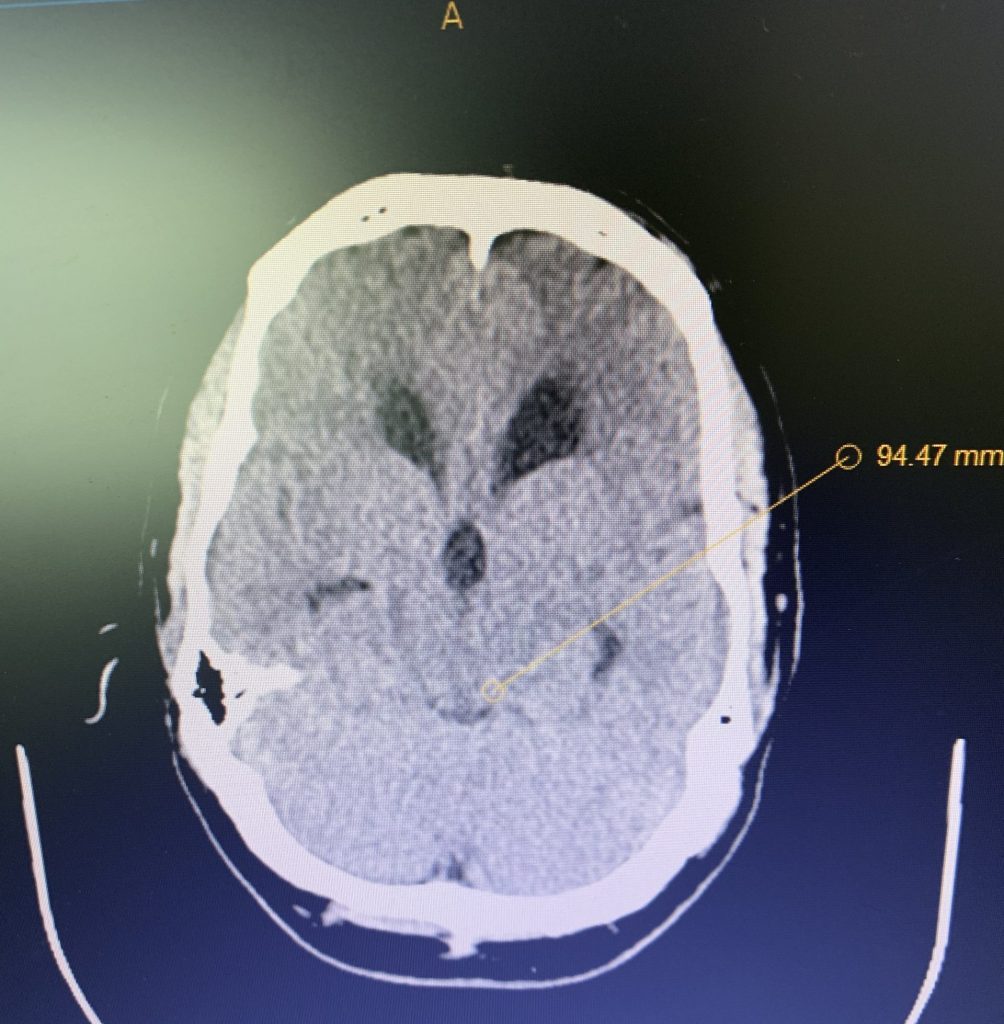

Figure 1A: Pre-operative MRI

Figure 1B,C: Pre-operative CT images.

Prior to shunting, a head CT was obtained and the head CT in addition to documenting a patten of obstructive hydrocephalus suggested a possible mass lesion compressing the aqueduct at its inferior aspect. Figure #1 demonstrates the hydrocephalus and the possible lesion. A decision was made at this point that the patient had obstructive hydrocephalus that was now symptomatic and he was taken for a laparoscopic-assisted ventriculoperitoneal shunt.